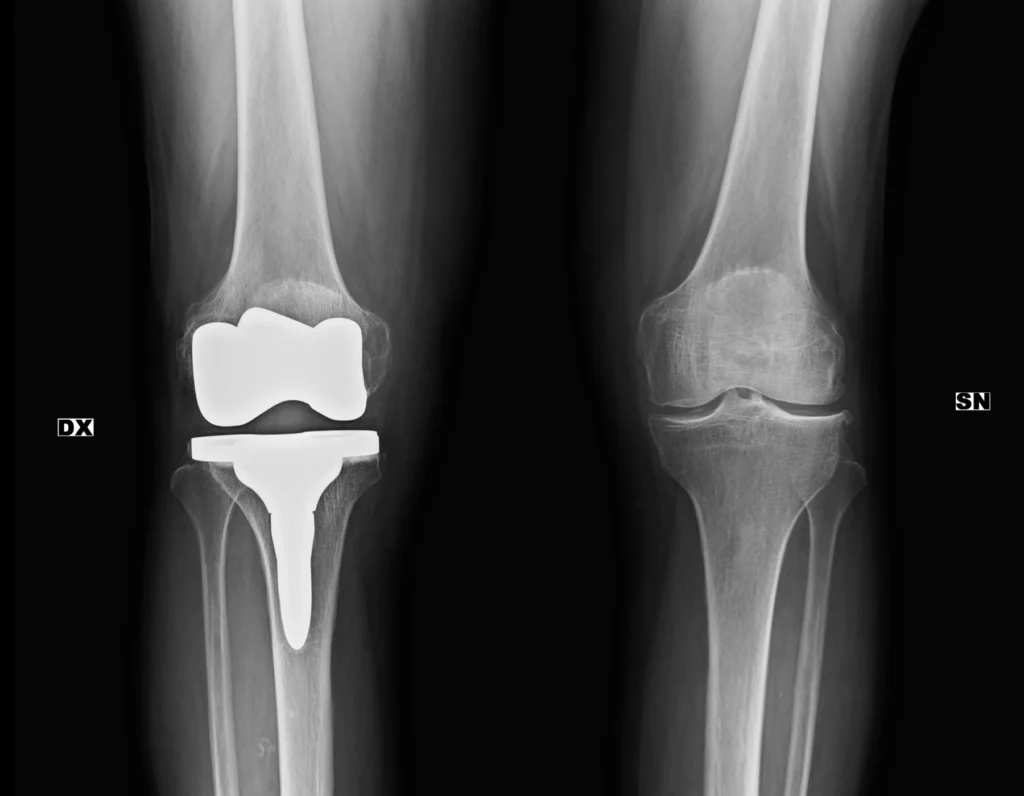

Radiografía simple de rodillas con prótesis metalica, utilizada como ejemplo docente para ilustrar la densidad metálica y su apariencia característica en la imagen radiográfica.

Presencia de prótesis bicompartimental de rodilla derecha, las estructuras intensamente radiopacas, corresponden a material metálico, que presentan una atenuación máxima de los rayos X.

La densidad metálica constituye el extremo superior de la escala de densidades radiológicas y se representa como imágenes blancas intensas en la radiografía.

Su reconocimiento es inmediato y no suele generar ambigüedad diagnóstica.

- El metal es la densidad más radiopaca.

- Aparece blanco intenso.

- Puede generar artefactos.